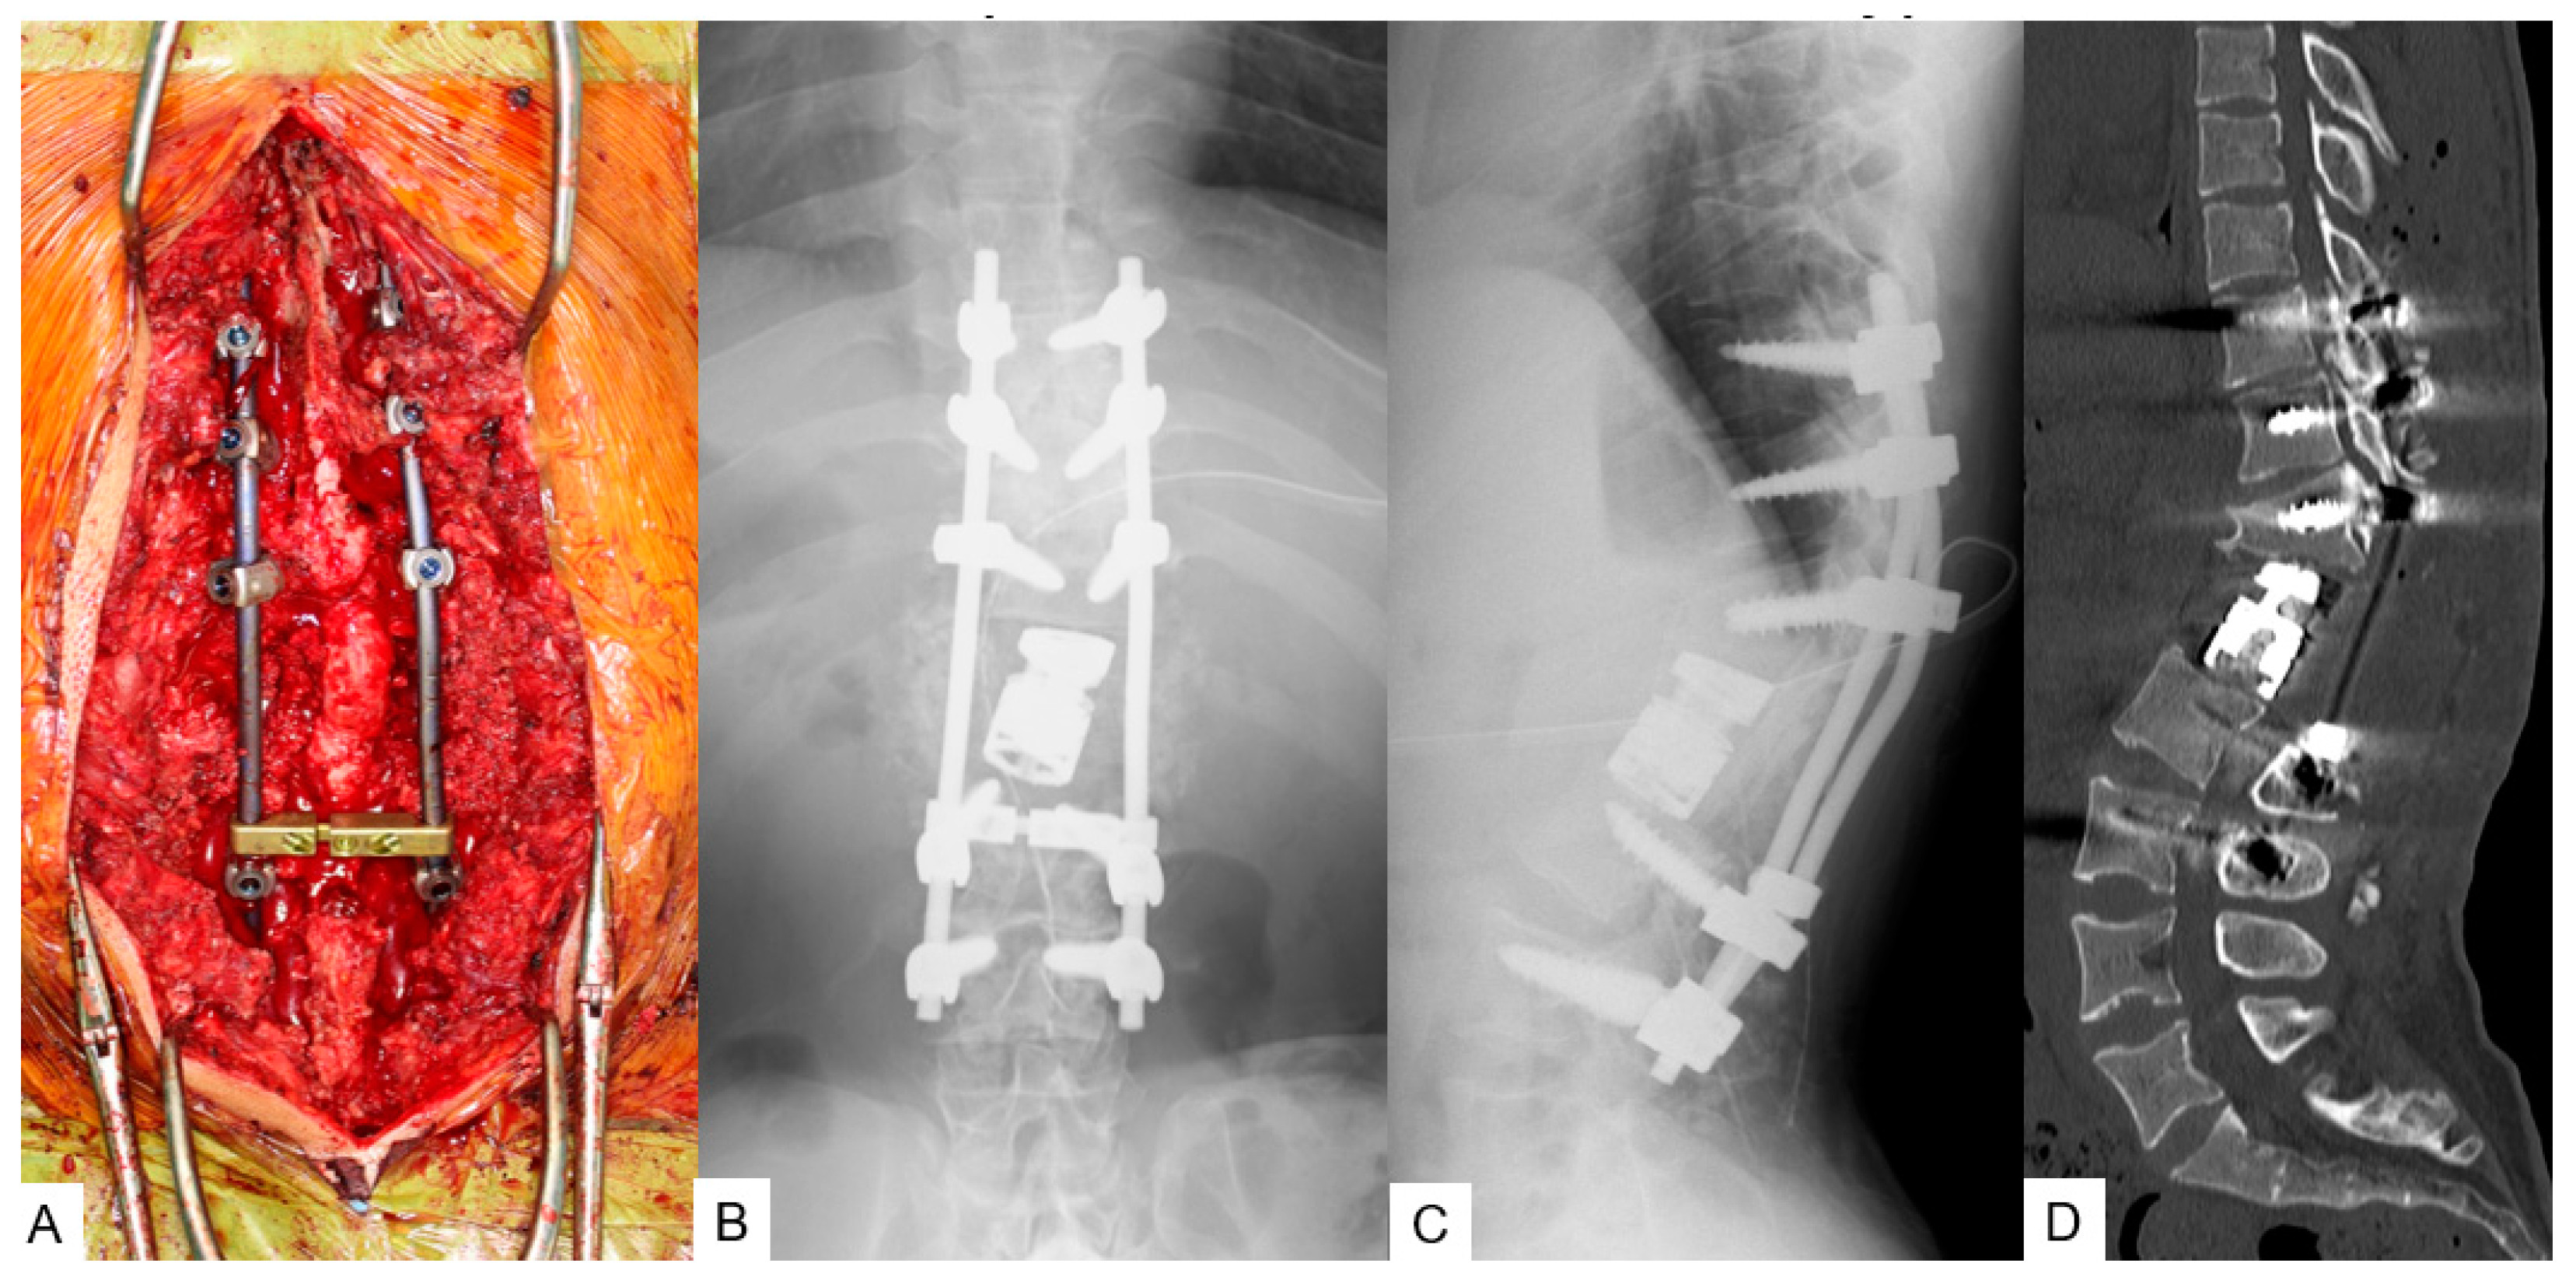

3.1.4. Surgery

3.1.5. Postoperative Imaging